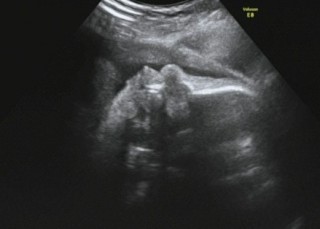

太ももの骨です(*^^*) あんまりお顔を見せてくれません(ノ_<。) 体重は、2,257gで順調とのことです(*^▽^*) 胎動も毎日元気いっぱいで愛しいです(*´ω`*)

ボクシングポーズの我が子。体重は2066gで、前回より61グラムしか増えておらず...でも標準範囲で、多少の誤差もあるから心配ないとの事。私の尿に糖が降りてしまったので、来週検査に。母体に糖が多すぎると、赤ちゃんが大きくなるのでと注意されました。食事もカロリーだけじゃなく、糖質にも気を付けたいと思います。